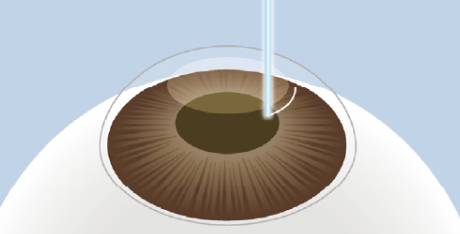

小切開の作成

約2~4mmの小さな切開を

角膜表面に作成します。